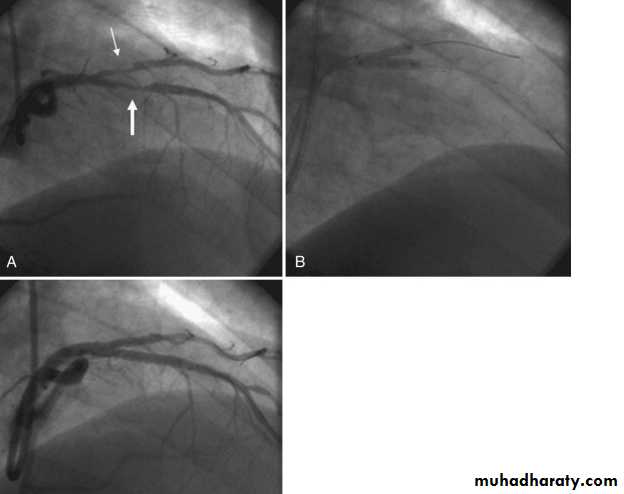

Severe proximal LAD Lesion

Very severe proximal LAD stenosis

Total CX Occlusion

Proximal LAD PCI

Bifurcational lesion PCI